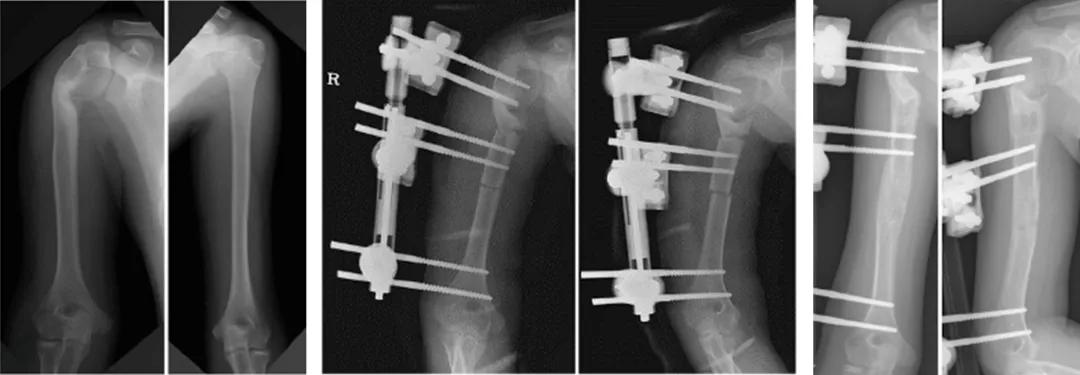

于前外侧入路,显露肱骨近端及内侧病变部,病变呈条索状。按术前设计,依次置入拟截骨近端螺纹导针,以140°php钢板固定(常用于儿童髋内翻矫正),固定远端锁定螺钉,截骨端达“端-侧对合”。

于上臂中远段,分别置入近端及远端外架半钉,并于两组半钉之间行微创截骨,固定外架。术中拍片示肱干角矫正满意。

图3a 肱骨近端病变去除、外翻截骨140°钢板固定 图3b 单臂外固定架固定、微创截骨